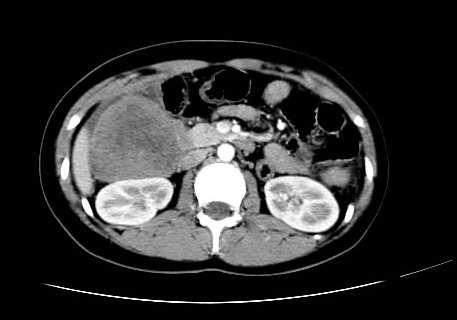

女 16岁  右上腹痛一天,无其他不适

肿块最大径位于十二指肠降段与水平段移行处,并且与肝脏压迹呈“0”形征,可以考虑位于肝外并与胃肠道关系紧密,考虑胃肠道间质瘤(gist)可能较大,须除外神经节起源肿瘤。

肿块与十二指肠关系密切,支持间质瘤诊断.肝脏与结肠均为受压改变.

右下腹巨大肿快,密度不均匀,内见坏死低密度区,边界清楚,与周边胀器明显有分界,未见强化,多考虑来源于间叶组织的良性肿物.

病灶巨大,少部分向肠腔内生长,大部分向长腔外生长。其密度不均匀,增强显示明显不均匀强化,并见有大片状始终不强化的不规则坏死液化区。虽然病灶中上部形态尚可,病人又如此年轻,但中下部形态、密度、强化特点强烈提示为恶性病灶。综上,我考虑本病例为:恶性胃肠道间质瘤。